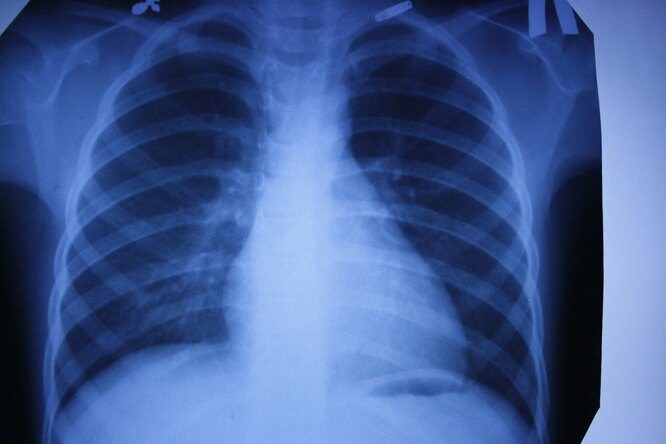

Рентгеновские снимки — первая в мире диагностическая визуализация. Сложно представить современную больницу без такого обследования. Это и флюорография для проверки наших легких, и снимки при заболеваниях суставов или переломах костей. Обнаружение на ранних стадиях туберкулеза или опухоли в легких увеличивает шансы на выздоровление. Кроме того, жесткое рентгеновское излучение может уничтожать раковые клетки. Принципы современной рентгеноскопии используются и в системах безопасности (сканеры в аэропортах, вокзалах и т. д.), и в производстве. В металлургии или машиностроении равномерность просканированной X-лучами структуры указывает на хорошие прочностные характеристики деталей. Таким же образом проверяются прочность бетонных конструкций для монолитного домостроения, сварные швы сложных металлоконструкций.